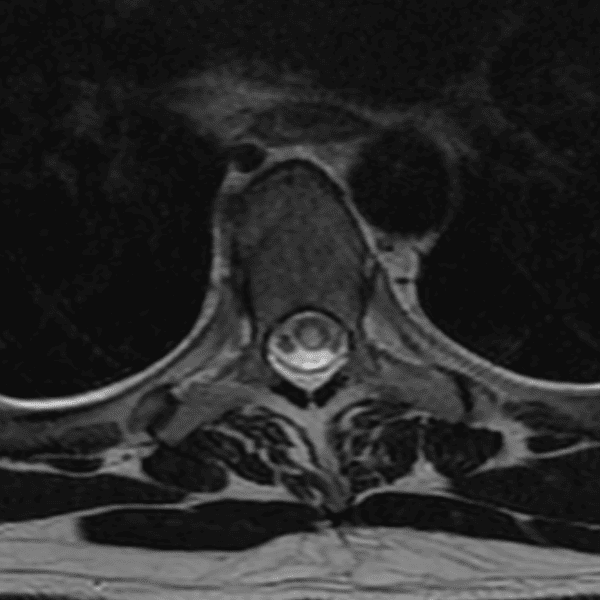

Simulates call by including subtle or difficult cases and some normals.

35 cases